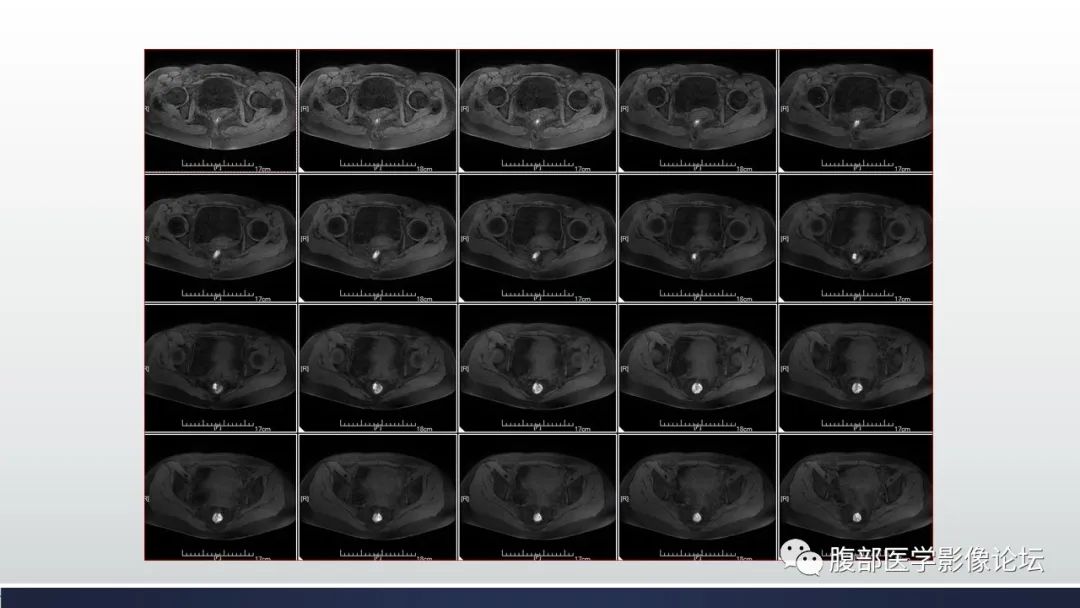

【病例】子宫内膜透明细胞癌1例MR-3